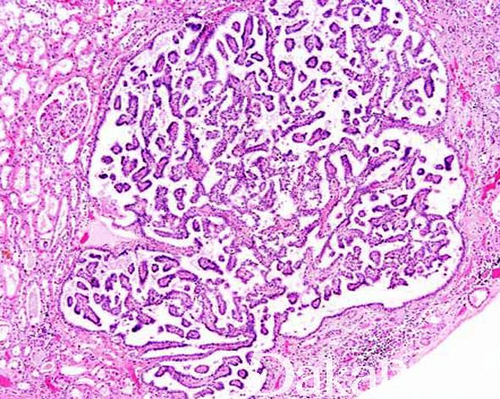

肾乳头周围包有肾小盏,每个人的肾大约有七八条肾小盏,肾小盏的形状对诊断肾脏病有很大的意义,如果患有肾乳头疾病,一般就有坏死的情况,常见的就是肾脏炎症,这种疾病容易造成肾脏结构改变,所以平时在生活中要做好疾病的预防。